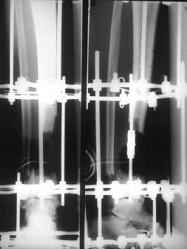

отделяемое. #1;#2. Стержневой апп. снят, наложен апп. Илизарова, дренажно-ирригационная система промывки раны. #3; #4. После стихания инфекции,